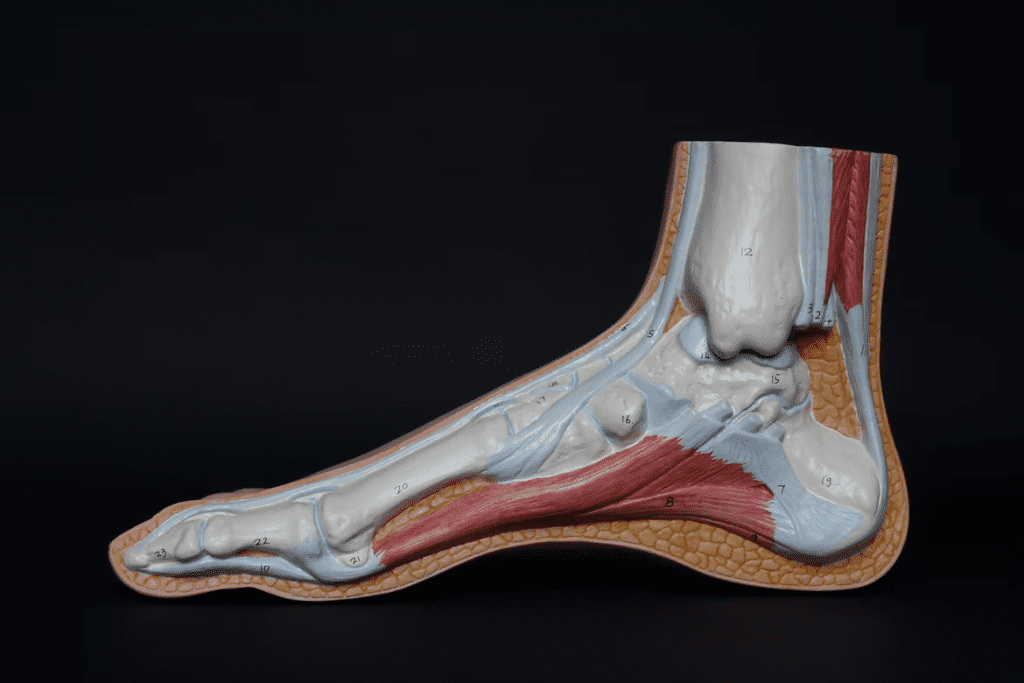

From capitalareapt.com

Physical Therapy for Bone Spurs Heel Spurs Remove Bone Spur Without Surgery There are several popular natural remedies for removing bone spurs without the use of surgery. Taking apple cider vinegar each day is said. Tell your healthcare provider if you develop. wall calf stretch. most patients with mild or moderate nerve compression and irritation from bone spurs can manage their. understanding bone spurs and why they occur is. Remove Bone Spur Without Surgery.